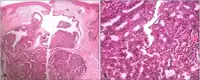

Micrograph of a papillary hidradenoma with the characteristic papillary structures and epithelium with apocrine snouts. A fragmented overlying epidermis is seen at the top of the image. H&E stain. a,b) Cells of lumina showed decapitation secretion similar to apocrine gland

a,b) Cells of lumina showed decapitation secretion similar to apocrine gland Intermed. mag.

Intermed. mag. Very high mag.

Very high mag.